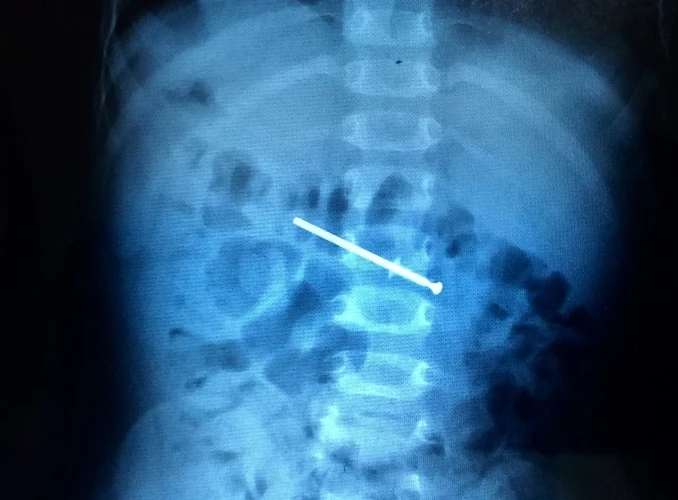

Cây đinh trong bụng bé trai

Theo BS Dũng, do cây đinh bén nhọn nên dị vật không thể cho ngoài qua đường tiêu tiện. Nếu bé nhập viện muộn, khả năng cây đinh kẹt ở tá tràng (phần đầu ruột non, ngay sau dạ dày) dễ gây thủng, xuất huyết và hoại tử. Hiện sức khỏe bệnh nhi đã ổn định.